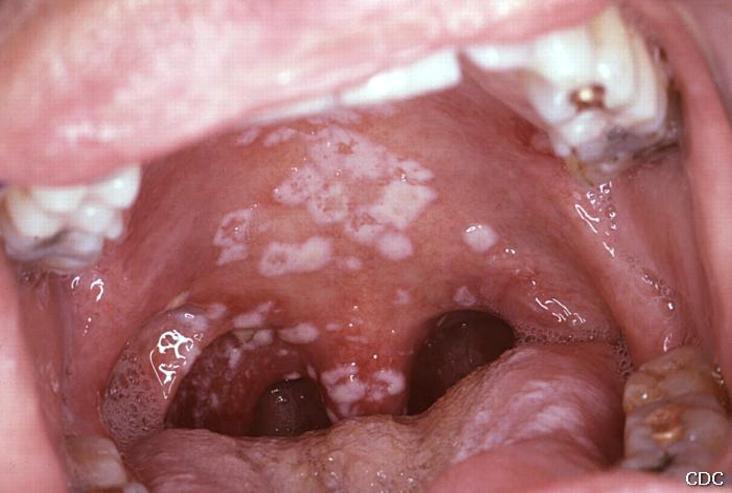

1. Candidosis bucofaríngea

1. Placas blanquecinas, adherentes, indoloras, aisladas o confluentes.

1. Pacientes jóvenes descartar VIH